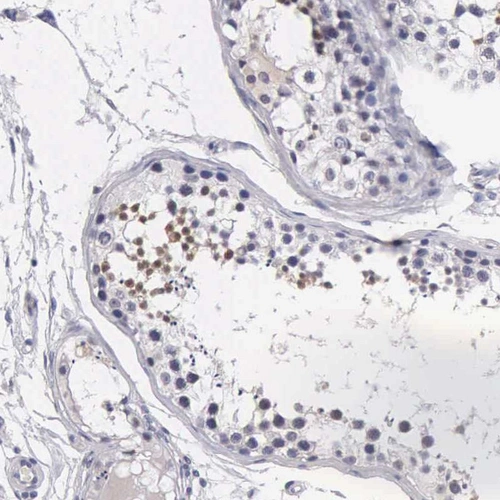

Immunohistochemical staining of human testis shows moderate nuclear positivity in cells in seminiferous ducts.